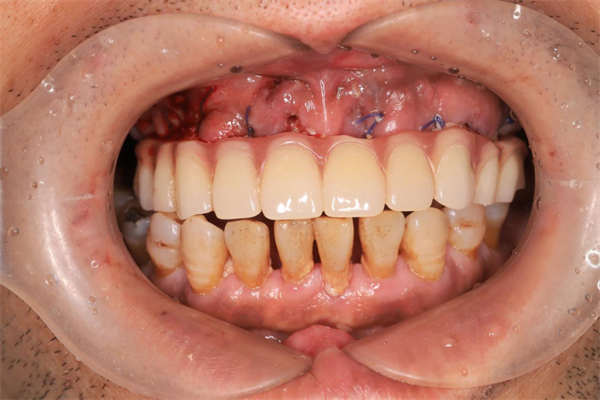

過渡義齒即刻戴牙(告別拔牙后缺牙期)

“數(shù)字化全口種植牙”目前在北上廣等經(jīng)濟發(fā)達地區(qū)開展較多,由于其難度大、設備要求高、技術依賴性大,陜西省開展較少。此手術的獨立開展意義重大,標志著西電集團醫(yī)院口腔科種植修復達到國內先進水平。

因即刻種植+3D數(shù)值化導板的引導,術中創(chuàng)傷小,精準度高,且無拔牙等待鑲牙時間,與傳統(tǒng)種植方式相比,大大縮短了手術時間,減小了手術創(chuàng)傷,減少了患者身體及精神負擔。